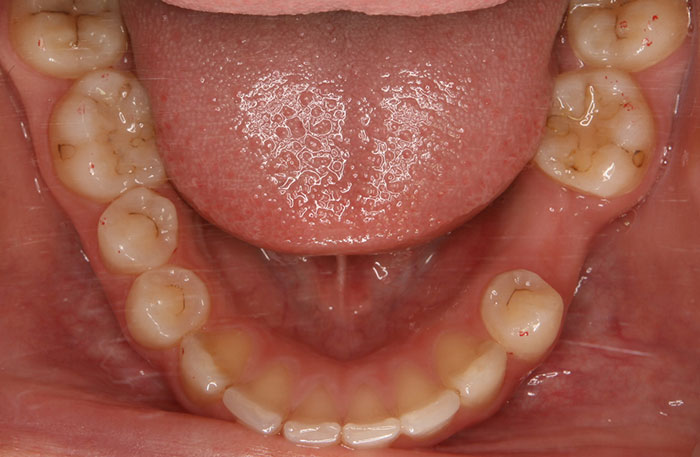

横になった親知らずの症例

Before

After

真横になった親知らずを抜歯したレントゲン写真です。